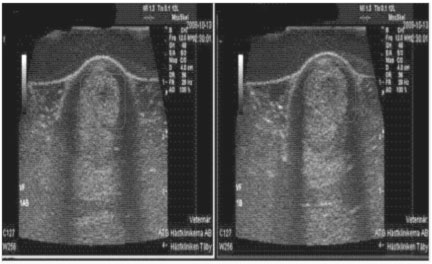

Example 2: 4 year old thoroughbred

Ultrasound Impressions: Image on the left shows a tendon injury. The series of images is taken over the course of 6 weeks, illustrating a steady improvement. At 6 weeks you can see healing was complete. This horse was treated for this injury twice daily on the Vitafloor.